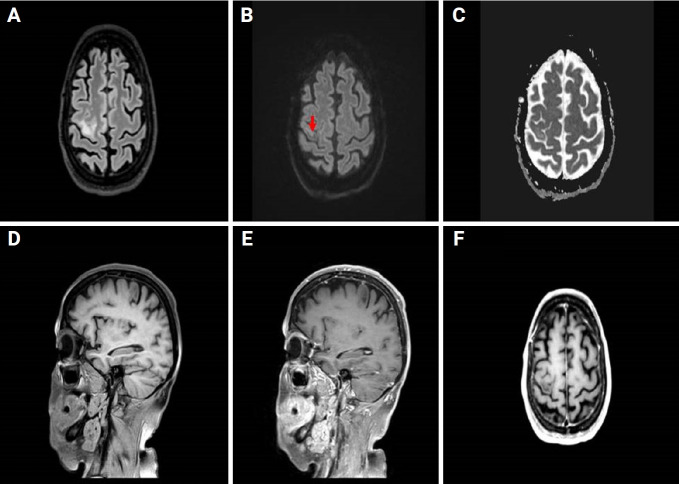

我们描述的情况下,一个47岁的妇女谁是困惑和抱怨左无力时,她提出了我们的机构。患者接受了头部计算机断层扫描,怀疑最近发生的缺血性发作(亚急性期)。患者住进神经内科,接受了磁共振成像(MRI)和造影剂治疗。临床和实验室结果以及MRI特征,特别是在敏感性加权成像(SWI)序列中出现低信号边缘,与进行性多灶性白质脑病(PML)的诊断一致。淋巴细胞减少导致免疫抑制,患者随后被诊断为先前未记载的艾滋病。我们的目的是在免疫功能低下的艾滋病患者中报道这一罕见的PML病例,描述其主要的MRI特征和SWI序列的可能作用。

We describe the case of a 47-year-old woman who was confused and complained about left-sided weakness when she presented to our institution. The patient underwent a head computed tomography that raised the suspicion of a recent-onset ischemic episode (subacute phase). The patient was admitted to the neurology department and underwent a magnetic resonance imaging (MRI) with contrast medium administration. The clinical and laboratory findings and the MRI features, particularly the presence of a hypointense rim in the susceptibility-weighted imaging (SWI) sequences, were consistent with a diagnosis of progressive multifocal leukoencephalopathy (PML). Immunosuppression was observed as a result of lymphopenia, and the patient was subsequently diagnosed with previously undocumented AIDS. Our aim is to present this rare case of PML in an immunocompromised patient with AIDS, describing the main MRI features and the possible role of SWI sequences.